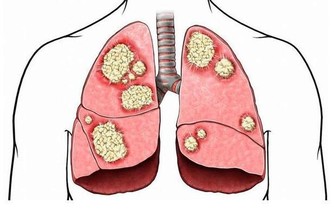

但實際上,鹼性磷酸鹽算是比較穩定的一類無機鹽,不是那種“輕佻的”、稍有“風吹草動”就會“改變立場”的物質。

常吃酸味食物,會影響骨骼發育,讓孩子長不高? 父母都該了解下

更重要的是,酸性食物被人體攝入後,並不是直接和骨骼接觸的,它要經過消化系統的消化吸收。

消化系統會根據體液的酸鹼情況,對營養物質進行“擇優錄取”——急需的、缺少的多吸收,反之則少吸收。

除此之外,人體的腎臟還是體內最重要的酸鹼平衡器官。

在腎功能正常的情況下,體內液體的酸鹼度將會維持在一個非常穩定的狀態(7.35~7.45)。體內酸多了,腎臟就會多排出酸,反之亦然。

這種非常穩定的酸鹼度,是不可能引起大量鹼性磷酸鈣鹽溶解這種“軒然大波”的。

可見,經常吃酸性食物,並不會引起骨骼內礦物質的溶解流失,更不存在影響長個子一說。